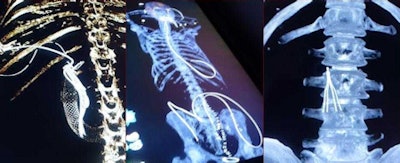

After the exam, CT images are transferred from the scanner to a life-sized touchscreen table (Anatomage, San Jose, CA) for display. This life-sized table is 3D-enabled, which allows manipulation of imaging data in multiplanar-reformation and volume-rendered modes.

Postmortem whole-body images are presented to the autopsy team members so they can visualize a 3D model of the case with lines, tubes, and instruments inside the body; find the visible abnormalities; and cut through the virtual body to localize the findings.